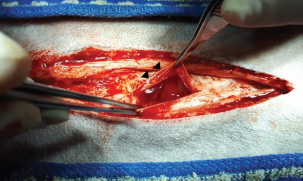

An 11-year-old intact male Siberian Husky was presented in acute hypovolemic shock. On physical examination, the patient was lethargic and exhibited tachycardia, tachypnea, and hypotension, with a recorded systolic/diastolic blood pressure of 58/31 mmHg. Abdominal radiographs were not diagnostic due to the loss of serosal detail secondary to intra-abdominal fluid accumulation. Hematologic evaluation revealed microcytic (mean cell volume, 58.4 fL; reference range, 61.6–73.5 fL) and normochromic (mean corpuscular hemoglobin concentration, 30 g/dl; reference range, 32–37.9 g/dl) anemia, with a packed cell volume (PCV) of 28.5% (reference range, 37.3%–61.7%). Additional abnormalities included hyperglycemia (231 mg/dl; reference range, 70–143 mg/dl), hyperamylasemia (4543 U/L; reference range, 500–1,500 U/L), hyperlipasemia (5,683 U/L; reference range, 200–1,800), and elevated D-dimer concentration (2 mg/dl; reference range, 0–0.3 mg/dl). Abdominal ultrasonography identified a well-circumscribed, round, lobulated mass measuring approximately 10 cm in diameter, located caudal to the stomach (Fig. 1). A large volume of peritoneal fluid was also present within the abdominal cavity (Fig. 2). Compared to the anechoic urine within the bladder, the peritoneal fluid appeared hyperechoic. Fluid collected via abdominocentesis showed a PCV of 28% (reference range, 37.3%–61.7%). Thoracic radiographs showed no evidence of pulmonary metastases or thoracic abnormalities.

Fig. 2. A large amount of echogenic peritoneal fluid (white arrowhead), indicative of bleeding, was detected in the abdominal cavity.